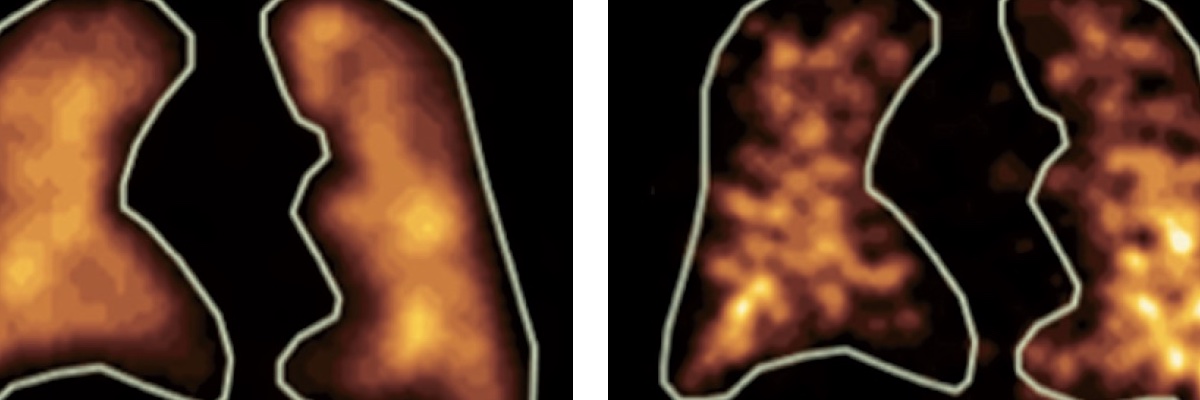

Les champs d'expertise numérique de l'équipe reposent sur les champs suivants : intelligence artificielle, image, analyse exploratoire de données, observabilité des données, analyse multiéchelle, morphologie mathématique, topologie discrète, filtrage spatio-fréquentiel, analyse dynamique, classification, décision, mesure de similarité, détection de changements, modélisation statistique.

Les champs d'expertise clinique de l'équipe reposent sur les modalités suivantes : imagerie par résonance magnétique (IRM), scanner (TDM), artériographie, imagerie nucléaire (TEP, TEMP), électroencéphalographie (EEG), échographie, imagerie préclinique (synchrotron). Les domaines cliniques privilégiés sont la néonatologie, la cancérologie, la neurologie, la radiologie, l'endocrinologie, l'urologie, l'histopathologie.